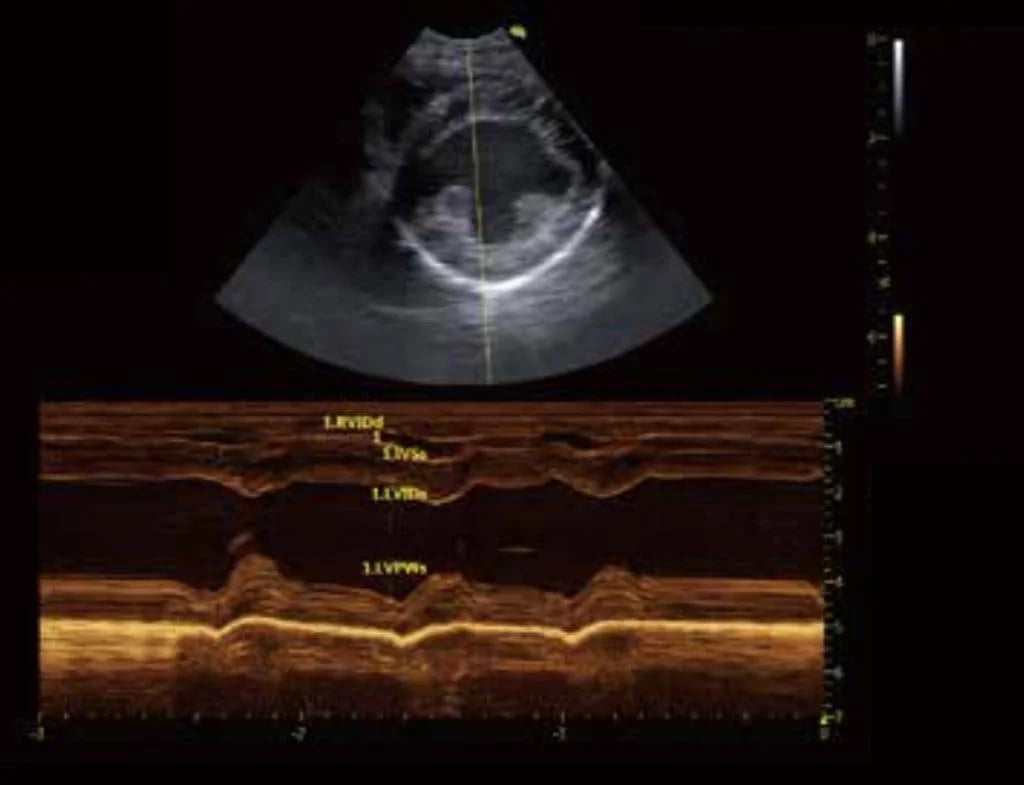

La ecocardiografía es una técnica de ultrasonido que ofrece una visión clara del funcionamiento del corazón de un animal en tiempo real. En la imagen, observamos un modo M, un corte transversal que se utiliza comúnmente para evaluar el tamaño de las cavidades cardíacas, el grosor de las paredes y la función del ventrículo izquierdo.

- La imagen se divide en dos partes:

- Imagen en modo B: La sección superior muestra un plano del corazón del animal, visualizando las cavidades cardíacas.Modo M (tiempo y movimiento): La sección inferior es la imagen en modo M, utilizada para evaluar el grosor de las paredes del ventrículo y su movilidad en cada ciclo cardíaco.